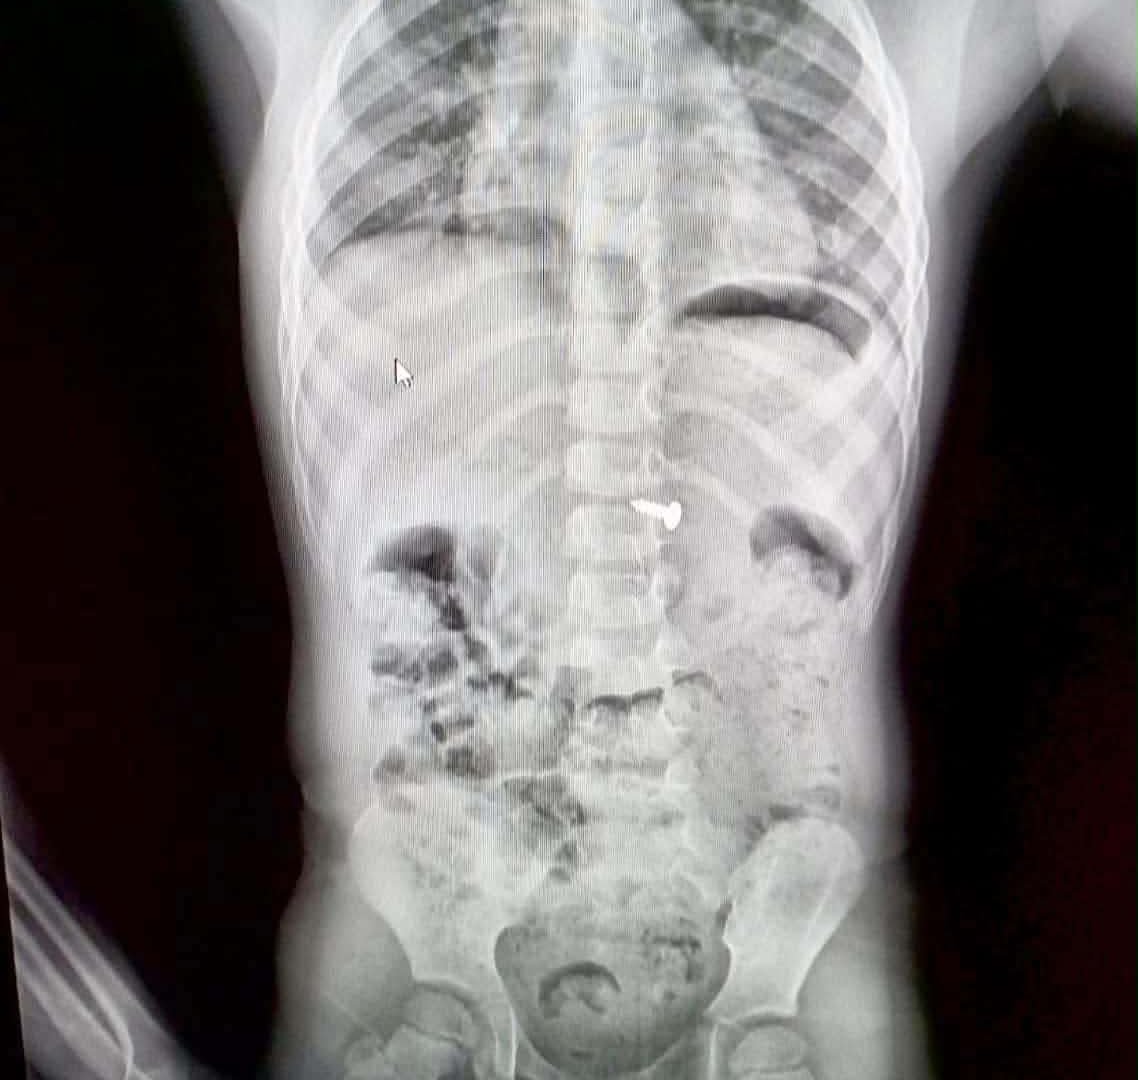

Діти пізнають світ на смак, і часто це призводить до небезпечних ситуацій. Проковтування дрібних речей — одна з найчастіших причин звернення до дитячих хірургів. Розповідаємо, які предмети несуть смертельну загрозу та як діяти батькам.

Деякі речі діють всередині організму як «тихі вбивці». Якщо дитина проковтнула щось із цього списку — негайно до лікарні:

Гострі предмети: Голки, шпильки чи уламки іграшок можуть травмувати внутрішні органи.